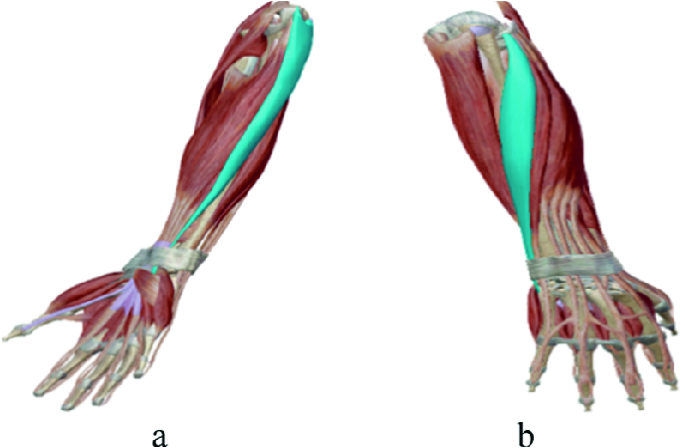

Анатомия мышцы Palmaris Longus